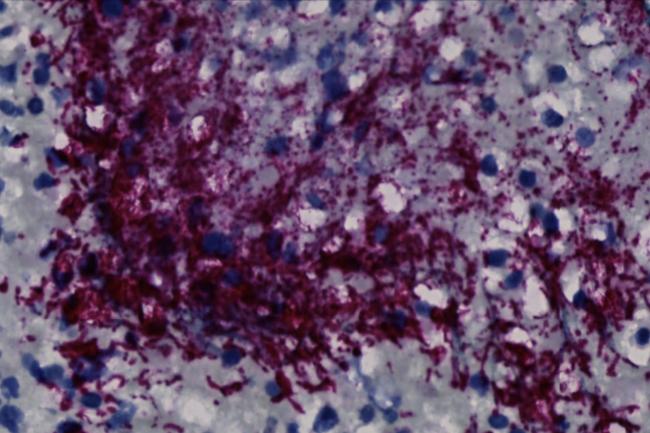

A bacteria implicated in gum disease, Fusobacterium nucleatum, has also been found in some colorectal cancer tumors. F. nucleatum is rarely seen in the guts of healthy people. Colorectal tumors harboring these bacteria are associated with more cancer recurrence and worse patient outcomes than tumors without them. However, it’s unclear how much of a role, if any, the bacteria play in causing the tumors to grow.

An NIH-funded research team led by Drs. Martha Zepeda Rivera, Susan Bullman, and Christopher D. Johnston of the Fred Hutchinson Cancer Center did a careful genetic comparison between F. nucleatum from colorectal tumors and those from healthy mouths. They analyzed the genomes of 80 F. nucleatum strains from the mouths of people without cancer and 55 strains from tumors of patients with colorectal cancer. The findings were published on March 20, 2024, in Nature.

The team found that one subspecies of F. nucleatum, called Fna, was more likely to be present in colorectal tumors. Further analyses revealed that there were two distinct types of Fna. Both were present in mouths, but only one type, called Fna C2, was associated with colorectal cancer.

When the researchers infected mice that had inflamed intestines (an animal model of colitis) with these two types of F. nucleatum, they found that mice infected with Fna C2 developed more tumors than those infected with the other type.